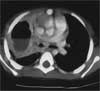

An inducedsputumexamination shows manypolymorphonuclear leukocyteswith no acid-fast bacteria. A cultureof the throat reveals typical flora.Results of a serologic test for cocciand a tuberculin skin test are negative.Results of 2 blood culturesare negative for pathogens. A CTscan of the chest shows a largecavitary lesion and air-fluid level inthe right upper chest; a thick, irregularcavitary wall; and adjacentcompression atelectasis (

Figure

).Empiric therapy with vancomycinand ceftriaxone is initiated.This is later changed to piperacillin with tazobactam, 1.5 g, every 8hours, and clindamycin, 120 mg, every 6 hours, to ensure coverage forGram-negative organisms. The patient becomes afebrile within 72 hoursand is transferred to a children's hospital for bronchoscopy and probablesurgery. Because she is doing well, the pulmonologist substitutes ceftriaxonefor the piperacillin with tazobactam and continues the clindamycin.One month later, radiographic evaluation shows considerable reduction inthe size of the abscess.